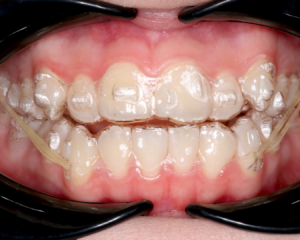

インビザラインのアタッチメントとは、マウスピース型の矯正装置であるインビザラインを歯にしっかりと固定し、歯の動きをコントロールするために歯の表面に接着される小さな突起のことです。

このアタッチメントがあることで、インビザラインは複雑な歯の動きをより精密に制御することが可能になります。単にマウスピースを歯に装着するだけでは、歯を回転させたり、傾斜させたりといった細かい動きをコントロールすることは難しいでしょう。ア

タッチメントは、マウスピースからの力を歯に効果的に伝達する役割を担い、治療計画に沿った歯の移動を実現するために不可欠な存在です。

これらのアタッチメントは、インビザライン治療において、歯を計画通りに動かすために重要な役割を果たしています。治療計画に基づき、患者さん一人ひとりの歯並びに合わせて最適なアタッチメントが選択・配置されるのです。

アタッチメントの大きさは、歯の位置や動き、そして治療計画によって異なります。一般的には、直径2~4mm、高さ1~2mm程度の小さなものです。米粒よりも小さいものが多く、それほど目立つものではありません。

◎アタッチメントはどんな形?

アタッチメントの形も、歯の位置や動きによって様々です。円形、楕円形、四角形など、様々な形があります。歯を効果的に動かすために、最適な形のアタッチメントが選択されます。

◎アタッチメントは目立つ?

アタッチメントは歯の色に近いレジンでできていますが、光が当たると多少の光沢感があるため、全く目立たないわけではありません。

しかし、非常に小さいので、会話する程度の距離ではほとんど気づかれません。また、歯の裏側に装着される場合もあります。気になる方は、歯医者さんに相談してみましょう。目立ちにくくする工夫として、歯の色に近い色のアタッチメントを選択することも可能です。